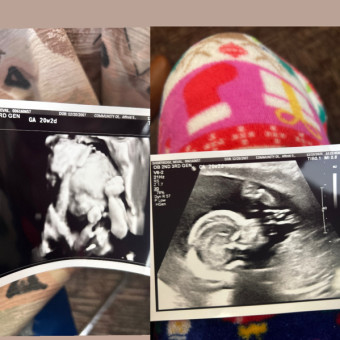

Nevaeh's Baby Registry

Nevaeh Shortridge

Summitville, IN

May 6, 2026

Everything is appreciated while we wait for the arrival for Zaniyah jade reneé!!🩷